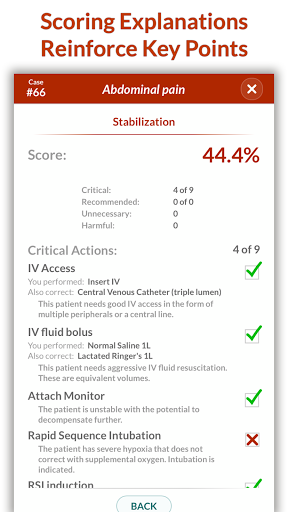

• Điểm số chi tiết và phân tích toàn bộ trường hợp - tìm hiểu điểm mạnh và điểm yếu của bạn

Các trường hợp có thể lặp lại vô hạn của Full Code đo lường các kỹ năng trong cả chẩn đoán và quản lý, cho phép bạn học hỏi từ những sai lầm của mình trong một môi trường không có rủi ro. Xây dựng năng lực để bạn có thể đối mặt với các trường hợp thực tế phức tạp một cách tự tin.